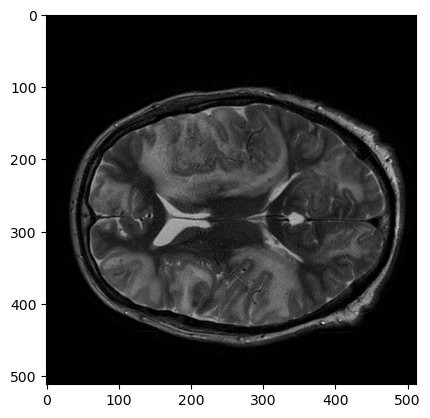

Для наглядности я взял T1 с контрастным усилением, SWI и T2. Т1-взвешенная серия нарезана сагиттально, SWI и Т2 – аксиально.

fig, axs = plt.subplots(nrows=1, ncols=3, figsize=(16,6))

axs[0].imshow(pydicom.dcmread(f'{resample_dir}/T1_CE/IMG-0003-00140.dcm').pixel_array, cmap='bone')

axs[1].imshow(pydicom.dcmread(f'{resample_dir}/SWI/IMG-0005-00046.dcm').pixel_array, cmap='bone')

axs[2].imshow(pydicom.dcmread(f'{resample_dir}/T2/IMG-0002-00030.dcm').pixel_array, cmap='bone')

Три серии